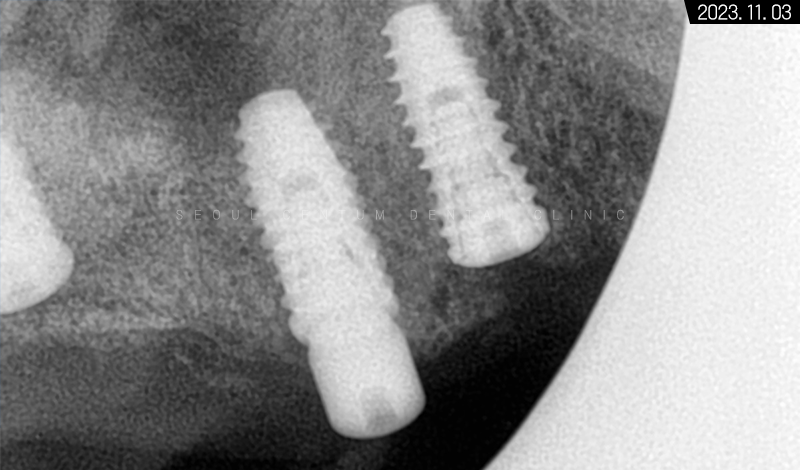

3개월이 더 지난 후 치근단 사진과 파노라마 엑스레이 사진으로 살펴봐도 초기 임플란트 식립 상황과 동일하게 견고히 자리 잡아 있는 것을 볼 수 있었습니다. 주위염도 생기지 않아 이상적인 결과를 만들어볼 수 있었어요.